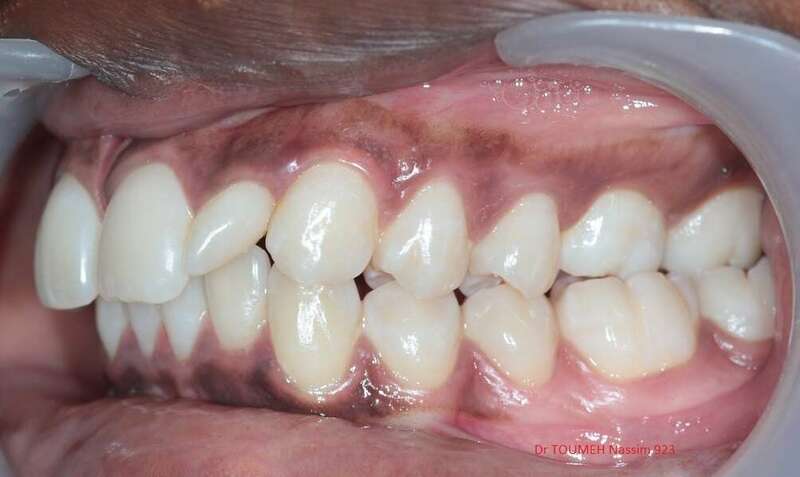

Latérales naines et orthodontie

la forme des dents influence grandement l’esthétique du sourire

La malformation des incisives latérales en est l'illustration

Le traitement consiste à redresser les dents à l'aide d'un appareil orthodontique (Multiattaches) et à redonner une forme normale aux dents malformées.

Dans ce cas présenté des couronnes provisoires en résines ont été posées.

Après